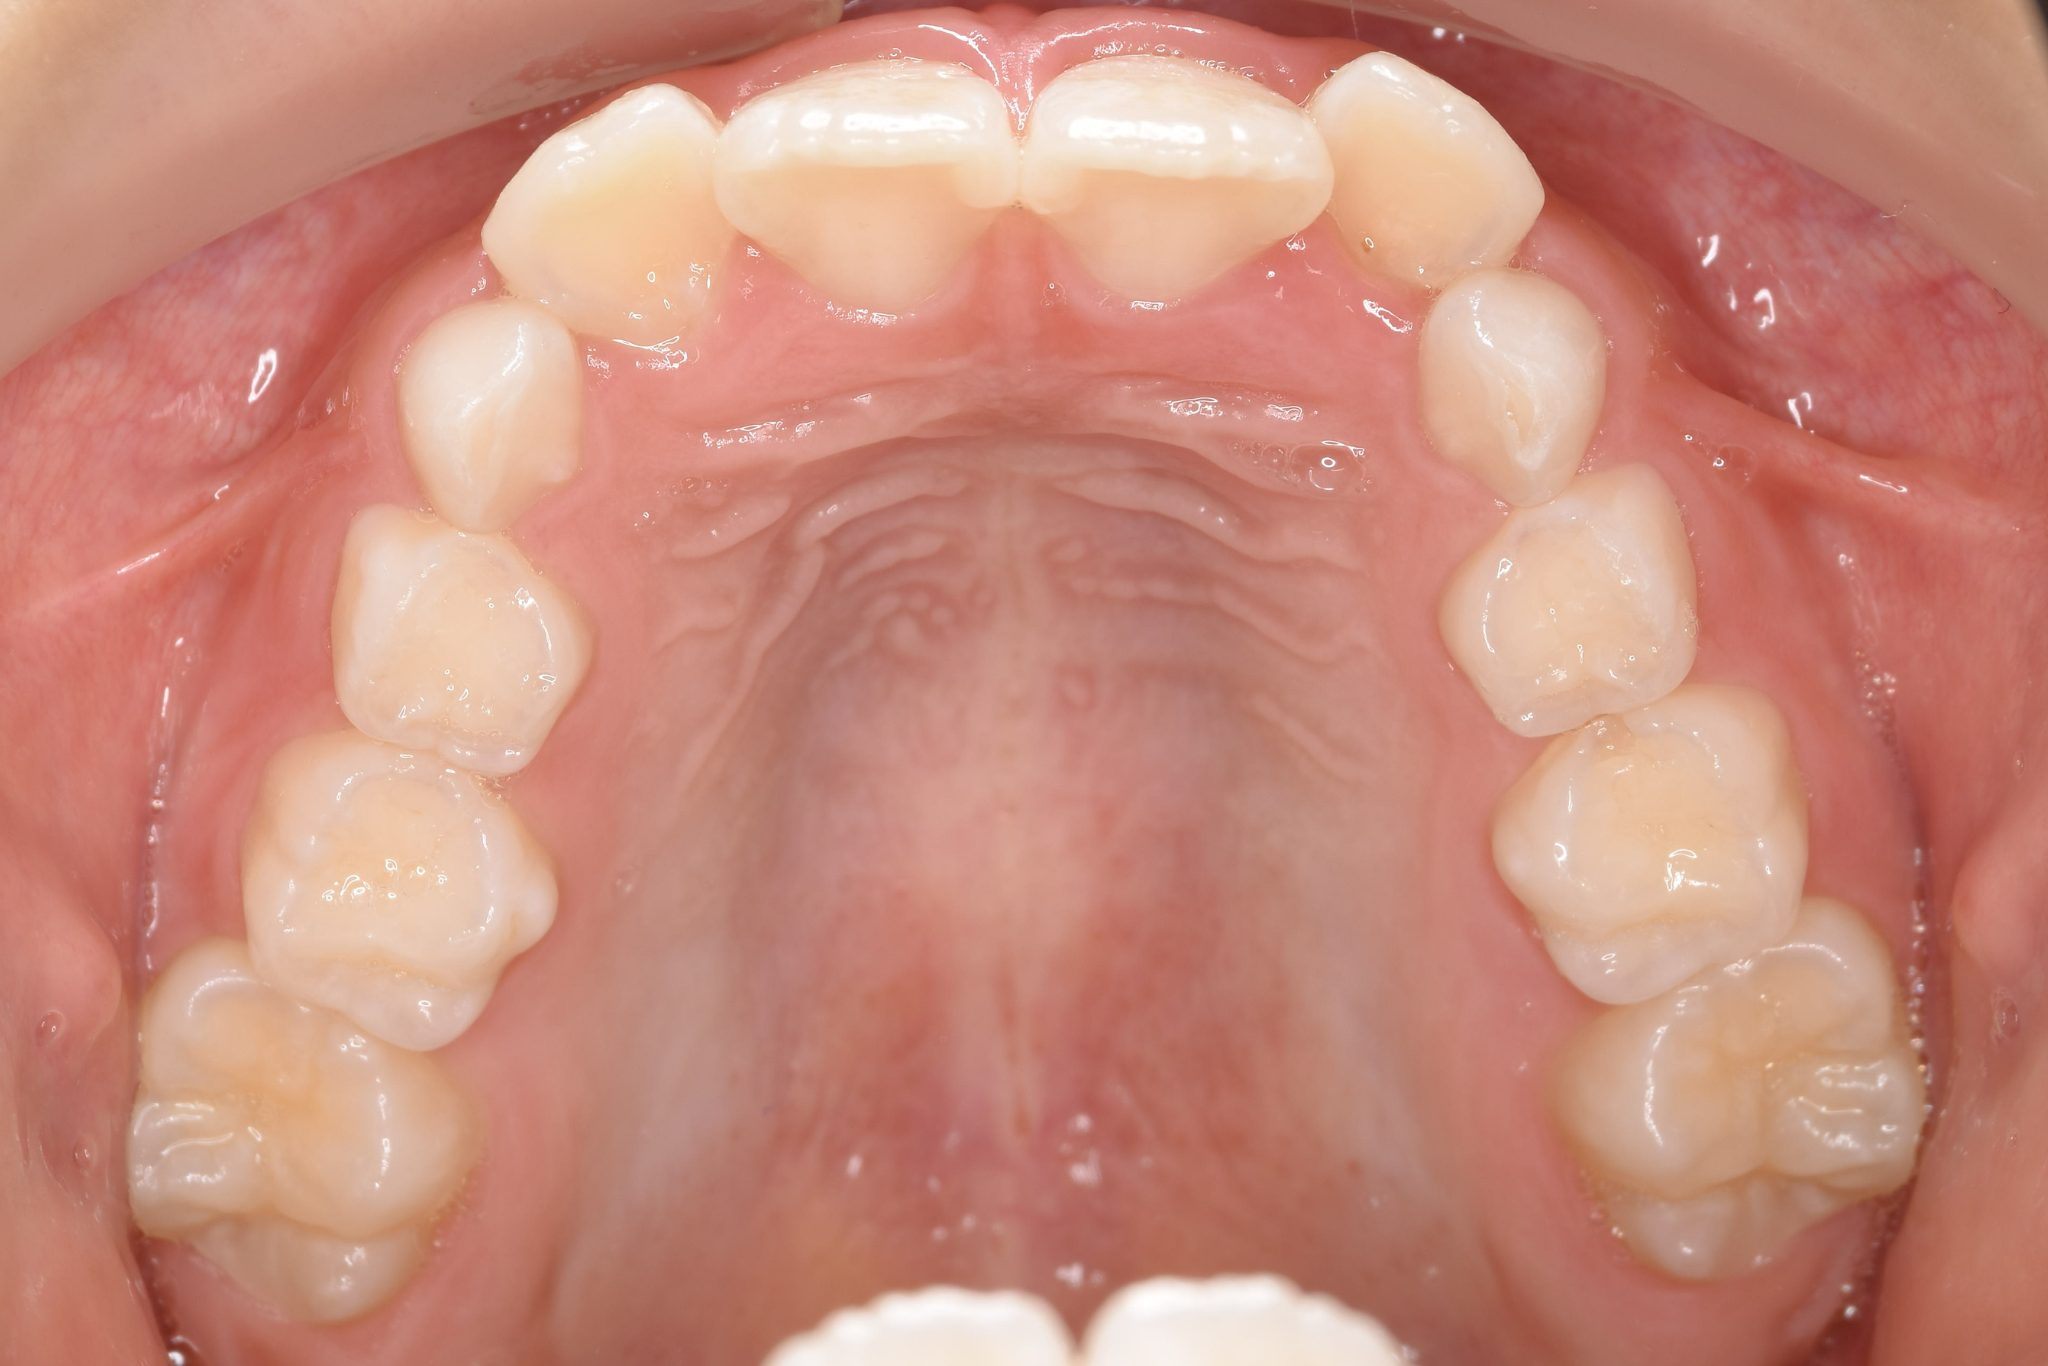

全顎ワイヤー矯正 症例_610 Case

ビフォー

| 主訴 | 前歯の歯並び|歯ぎしり |

| 施術内容 | 小児矯正1期治療 |

| 治癒期間 | 2年4か月間 |

| 費用 | 711,700円(税込) |

| リスク・副作用 | 違和感、不快感、痛み |